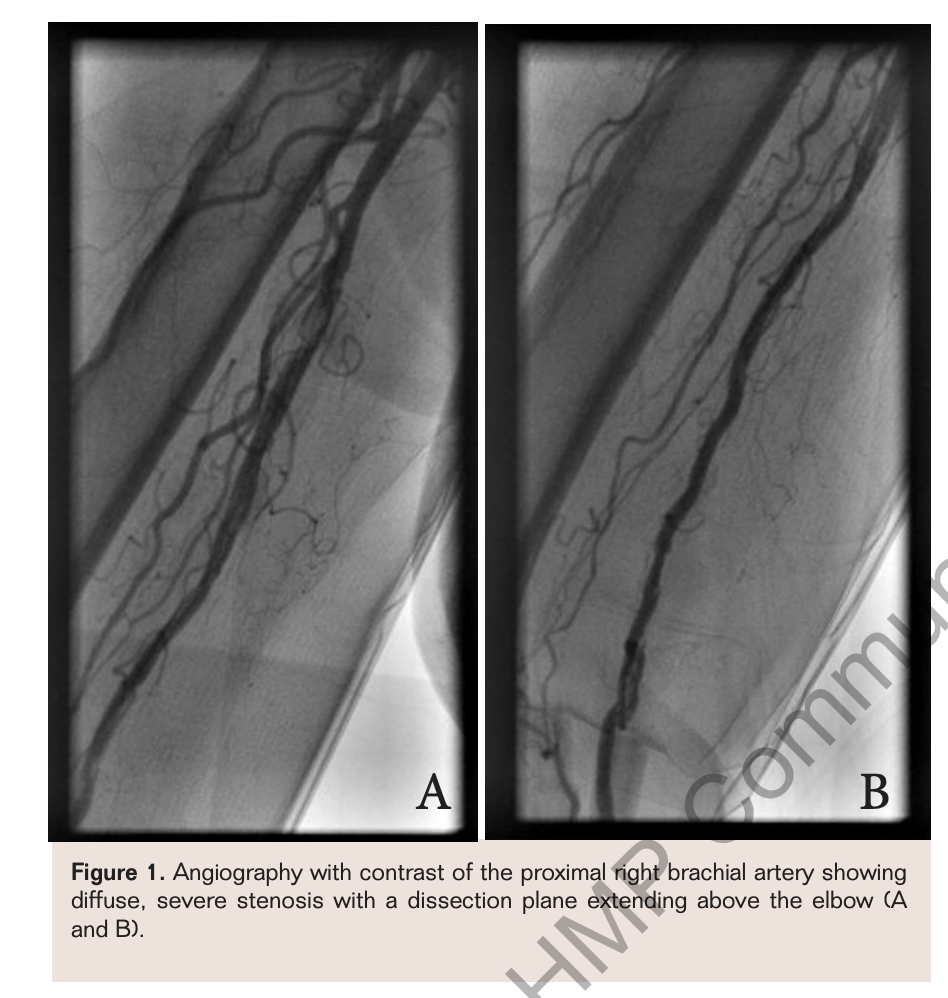

A more proximal 8 mm x 80 mm LifeStent FlexStar XL was deployed and then post dilated with the Fox Plus 6 mm x 120 mm PTA catheter. Final angiograms revealed a widely patent lumen. Post intervention examination revealed that the right brachial, radial, and ulnar pulses were restored: 2+ brachial, 1+ radial, and trace ulnar. An upper extremity ultrasound of this patient at 6-month follow-up and 18-month follow-up was consistent with healthy flow in her right brachial, radial, and ulnar arteries with continued stent patency (Figures 2 and 3).